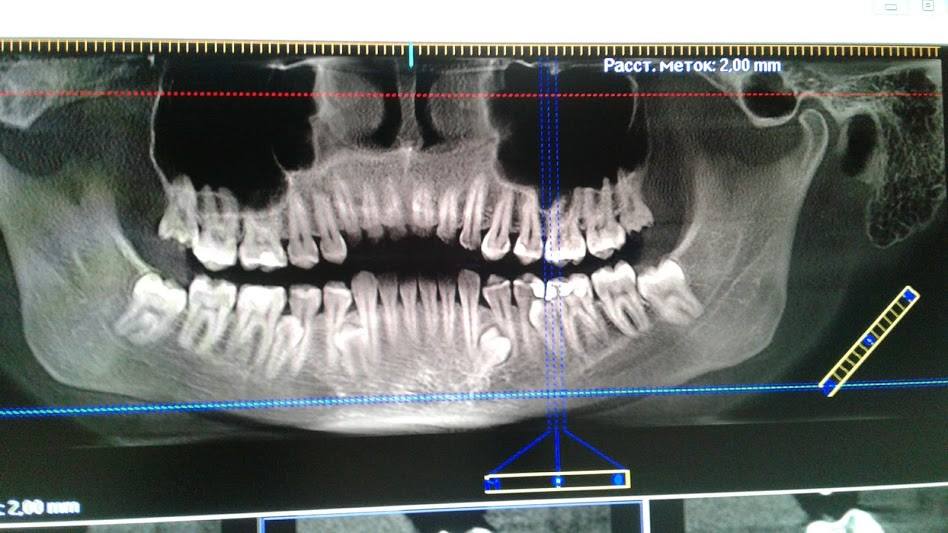

Найзубастіша в Україні жінка Юлія Фоміна живе у Світловодську Кіровоградської області і працює бухгалтером. Жінка-акула має 36 постійних повноцінних зубів. Про це заявила керівник Національного реєстру рекордів України Лана Вєтрова на своїй сторінці в Facebook.

За словами Вєтрової, чотири додаткових корінних зуба - рідкісна аномалія, яка підтверджена рентгенівськими знімками і висновками лікарів Стоматологічної клініки доктора Дахно.